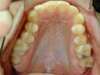

Intra Orale Supérieure

Intra Orale Inférieure